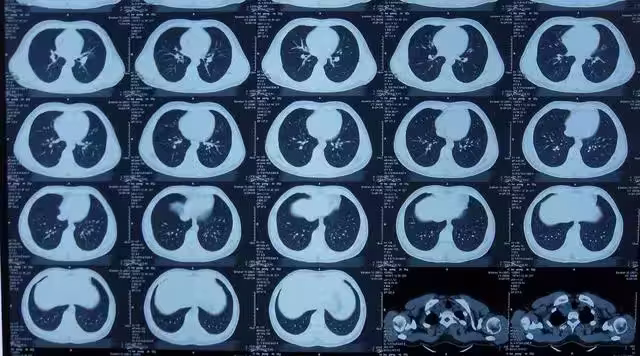

由於CT檢查的輻射劑量在安全範圍內,許多人可能會認為CT檢查是相對安全的,可以放心進行,然而,這並不意味著CT檢查沒有任何風險。

事實上,CT檢查仍然存在患癌症的風險,根據相關研究,一次效劑量為10mSv的成人腹部CT檢查將使癌症風險增加1/2000。

此外,國際輻射防護委員會(I-CRP)的研究數據表明,CT全身掃描體檢將使受檢者的輻射致癌風險增加約8%。

這意味著,如果一個人經常接受CT檢查,他們患癌症和遺傳病的風險會隨著接觸次數的增加而增大。